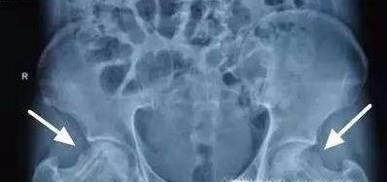

03、常见疾病肱骨头最常见的疾病就是肱骨头坏死,又称无菌性股骨头坏死。发病原因是肱骨头供血不足,进而导致肱骨头骨质坏死。

04、股骨头为什么会坏死:髋关节的负重太大。大家都知道髋关节是人体最大的关节,它支撑着整个躯干的重量,头与臼之间压力必然增大,长期保持着这种较大的压力,不但容易造成结构上的损伤,而且影响局部的血液环。

07、股骨头的血供少。股骨头的血供主要依靠囊外动脉环发出的外侧支持带和内侧支持带动脉,血管的吻合支量少且薄弱,当一支血管被阻断而另一支不能及时代偿时,即会造成股骨头的供血障碍。

08、有因才有果。据不完全统计有将近四十多种因素都能导致股骨头坏死。大致股骨头坏死可分为创伤性和非创伤性两大类,前者主要是由股骨颈骨折、髋关节脱位等髋部外伤引起,后者在我国的主要原因为酗酒、激素、先天因素等造成。除此之外,风、寒、湿的环境、减压病(长期从事潜水、飞行工作)等因素也会影响股骨头的血运,易发股骨头缺血性坏死。自己对号入座吧。